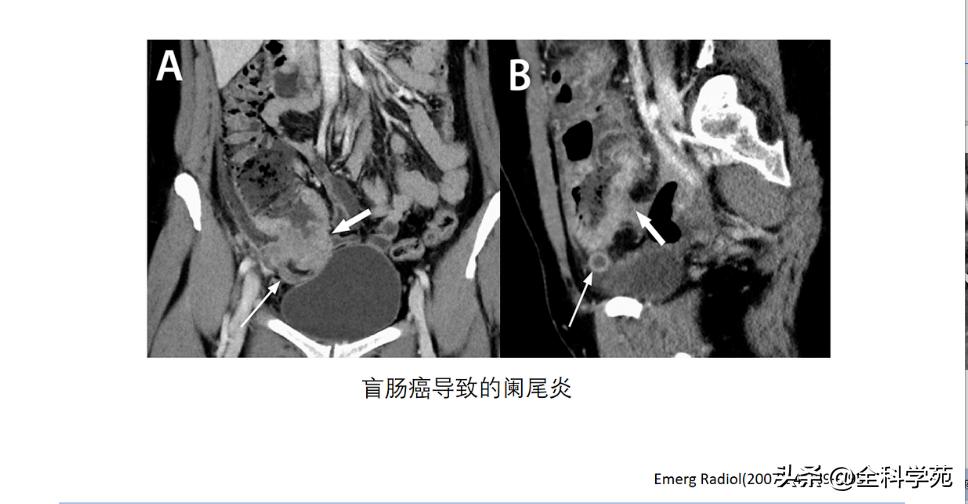

◆ 穿孔 (Perforation)

◆ 蜂窝织炎和脓肿 (Phlegmon and abscess